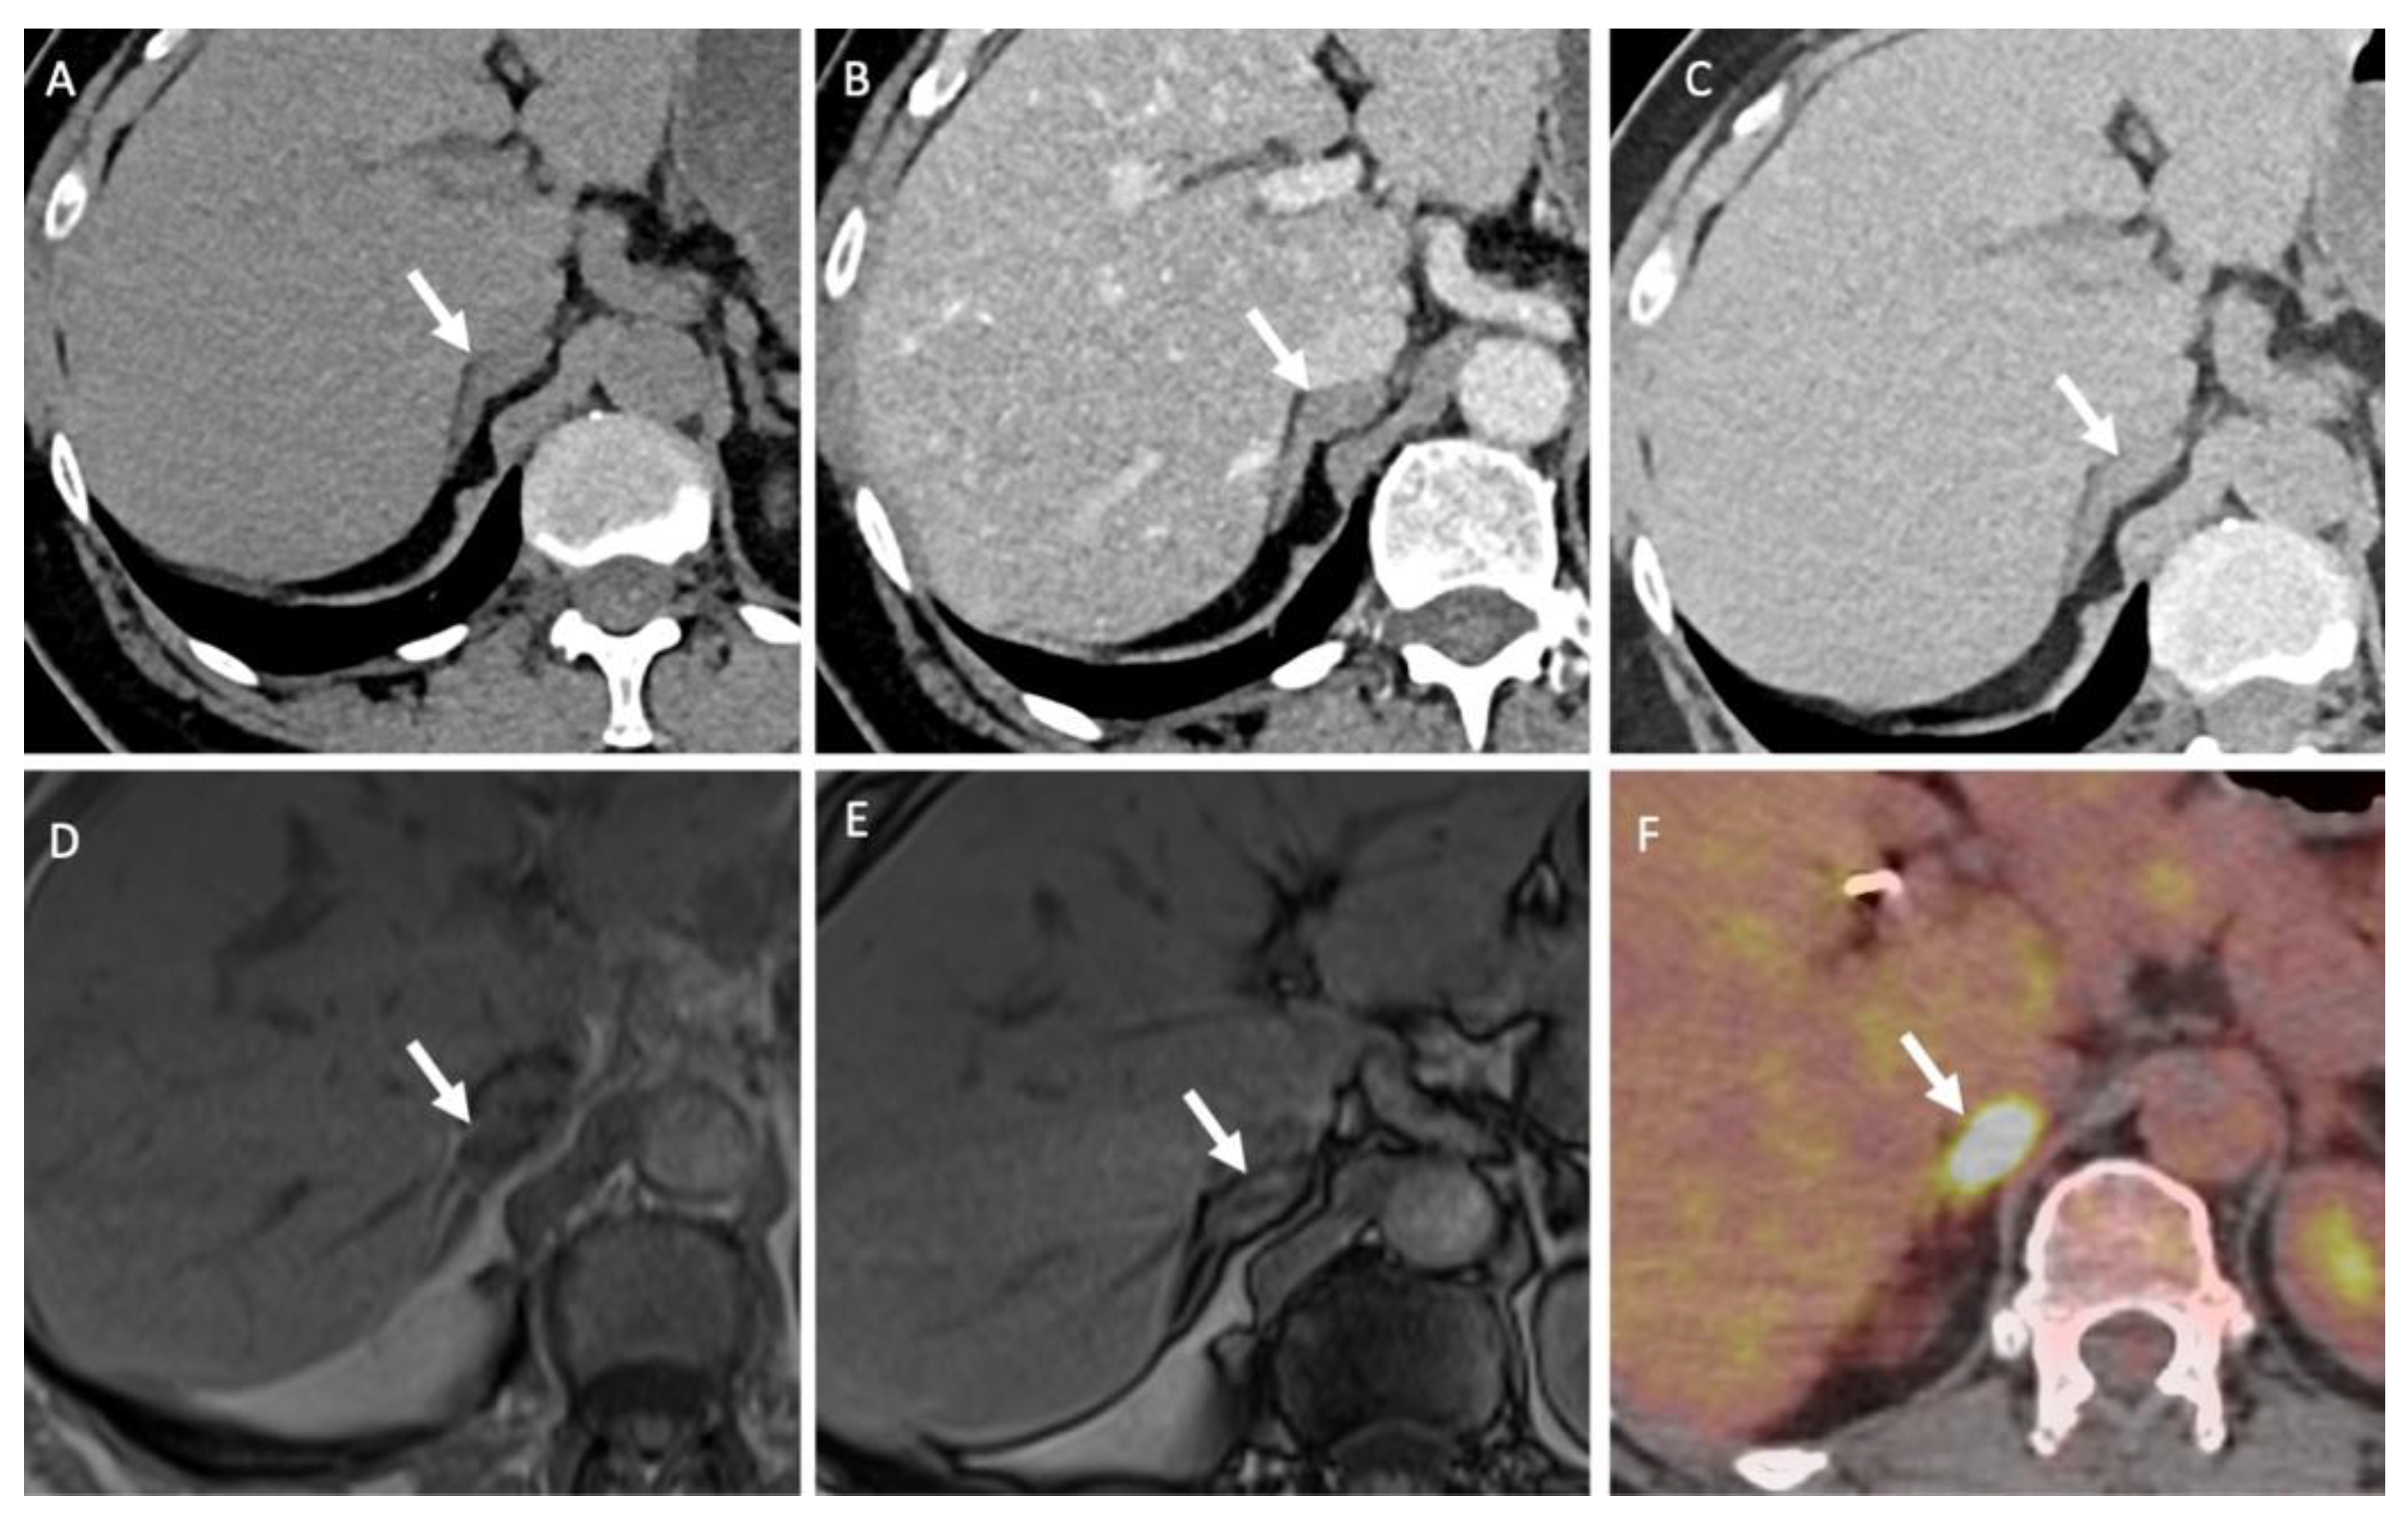

- Nagayama, Y.; Inoue, T.; Oda, S.; Tanoue, S.; Nakaura, T.; Ikeda, O.; Yamashita, Y. Adrenal Adenomas versus Metastases: Diagnostic Performance of Dual-Energy Spectral CT Virtual Noncontrast Imaging and Iodine Maps. Radiology 2020, 296, 324–332. [Google Scholar] [CrossRef]

- Lestra, T.; Mule, S.; Millet, I.; Carsin-Vu, A.; Taourel, P.; Hoeffel, C. Applications of dual energy computed tomography in abdominal imaging. Diagn. Interv. Imaging 2016, 97, 593–603. [Google Scholar] [CrossRef]

- Connolly, M.J.; McInnes, M.D.F.; El-Khodary, M.; McGrath, T.A.; Schieda, N. Diagnostic accuracy of virtual non-contrast enhanced dual-energy CT for diagnosis of adrenal adenoma: A systematic review and meta-analysis. Eur. Radiol. 2017, 27, 4324–4335. [Google Scholar] [CrossRef] [PubMed]